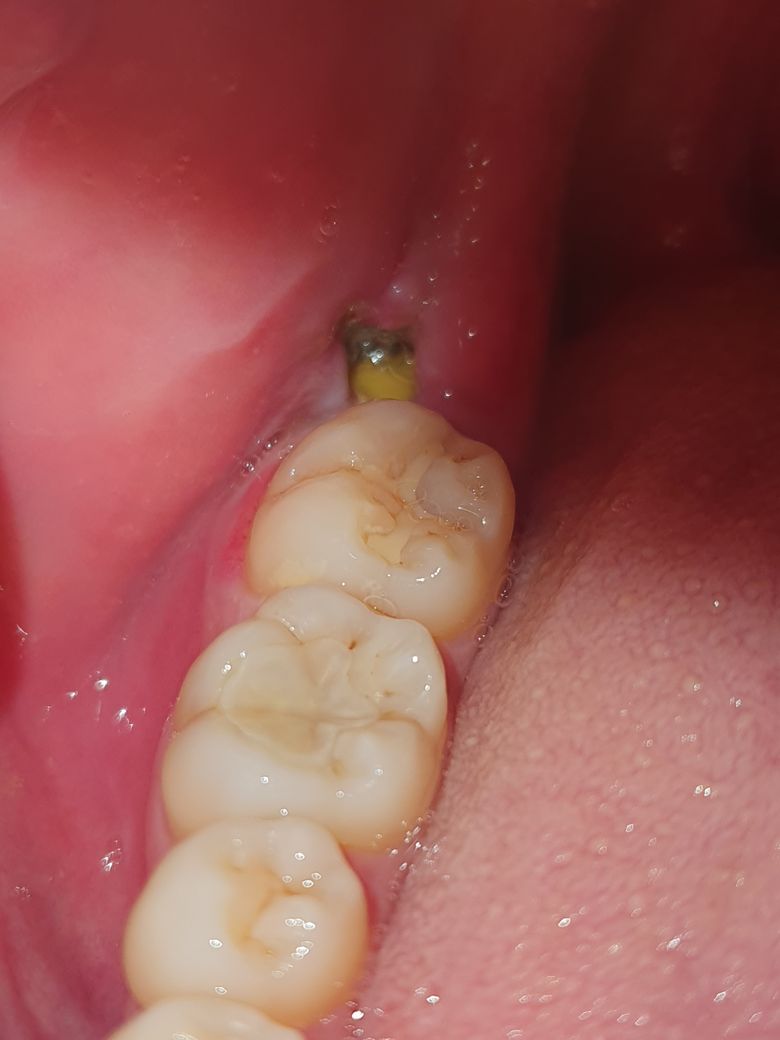

추가로 사랑니 뺀 곳인데

드라이소켓이나 이런건 아닐까요

저 상처부위에 노란색은 뭘까요

드라이 소켓은 아니며, 해당부위에 혈병이 생긴 것으로 보입니다. 억지로 제거하지 말고 그냥두길 권하며, 사랑니발치후에 1-2주정도는 통증 및 붓기가 동반되기에 통증이 있는 경우 소염진통제를 구매하여 복용하길 권합니다.

사랑니를 발치하고 발치한 부위에 혈병이 잘 유지되지 않았다면 드라이 소켓이 생길 수 있습니다.

드라이 소켓이 생겼을 경우에는 통증도 있지만 냄새도 동반하기 때문에 냄새가 심하게 나지 않는다면 드라이 소켓이 아닐 가능성이 높습니다.

안에 보이는 물질은 이물질이 들어갔을 수도 있고 잇몸이 차오르면서 생긴 가피일 수도 있습니다 정확한 확인을 위해서 치과에서 진료를 받아 보는 것을 권해 드립니다.